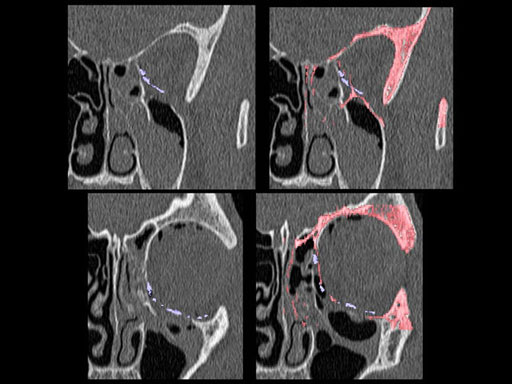

Furthermore, as orbital floor fractures are quite frequently associated with medial wall fractures; anatomic restoration especially in the transition zone between both wall is a demanding procedure. As described by B. Hammer, the orbital floor has an initial shallow convex section behind the rim, then inclines upward behind the globe, and inclines upward to meet the medial wall, creating a distinct bulge behind the globe. These convex curves of the medial wall and floor create a postbulbar constriction of the orbital cavity, which must be reconstructed when the orbit is rebuilt following fractures. Treatment is directed at precise anatomical reconstruction of orbital shape and volume in order to restore the correct position of the eye. To provide surgeons with an adequate implant that addresses the requirements of two wall acute orbital fractures or for secondary reconstruction of enophthalmos and dystopia, a new series of preformed orbital plates was developed for the new orbital matrix system.

These pre-formed orbital plates were developed based on the evaluation of more than 3000 CT scans of patient data and then reduced to 279 in order to find anatomical averages. In the end it was possible to reduce the number of plates down to two per side and still match the vast majority of all patients including males and females.

Unlike the existing two-dimensional mesh implants, the geometry of the new preformed plates will be adequate to match the individual anatomic situation of the patient in almost any case. However, the mesh parts can be individually adjusted if necessary. In these cases the solid part in the central posterior area needs to remain untouched. Areas of the orbit that do not require a bridging can be spared out by trimming the implant along the designated cutting lines in the height of the medial wall and/or length of the orbital floor area. The lateral anterior part of the plate is intentionally pre-bent higher than the orbital rim anatomy to allow free plate movement during plate positioning.

Implant placement according to the orbital landmarks

1 Orbital rim, 2 Inferior orbital fissure, 3 Posterior orbital ledge, 4 Transition between the medial wall and orbital floor, 5 Optic canal, 6 Lacrimal fossa